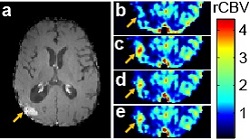

• Xin Li is currently interested in dynamic imaging data-acquisition optimization and modeling. One recent work proposed an improved leakage correction method for Dynamic Susceptibility Contrast MRI using gadolinium (Gd) based contrast agents. Using intravascular Fermmoxytol as reference, relative cerebral blood volume (rCBV) obtained with the new method (d) provides the best match to that offered by Ferumoxytol (e) when compared to alternatives (b and c, click right image to enlarge).